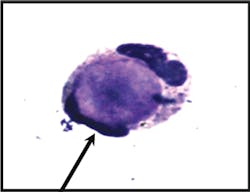

laboratory evaluation. On examination of a Wright-Giemsa stained cytospin

preparation, a single lupus erythematosus (LE) cell was identified,

characterized by homogenous nuclear material engulfed by a neutrophil (see

Image 2a). The cell was present in a background of numerous segmented

neutrophils, lymphocytes, plasma cells, and macrophages.

Image 2aLE cell: Wright-stained smear of the pleural fluid shows a typical single LE

cell consisting of a neutrophil with flattened nucleus engulfing a central

paler homogenous mass.